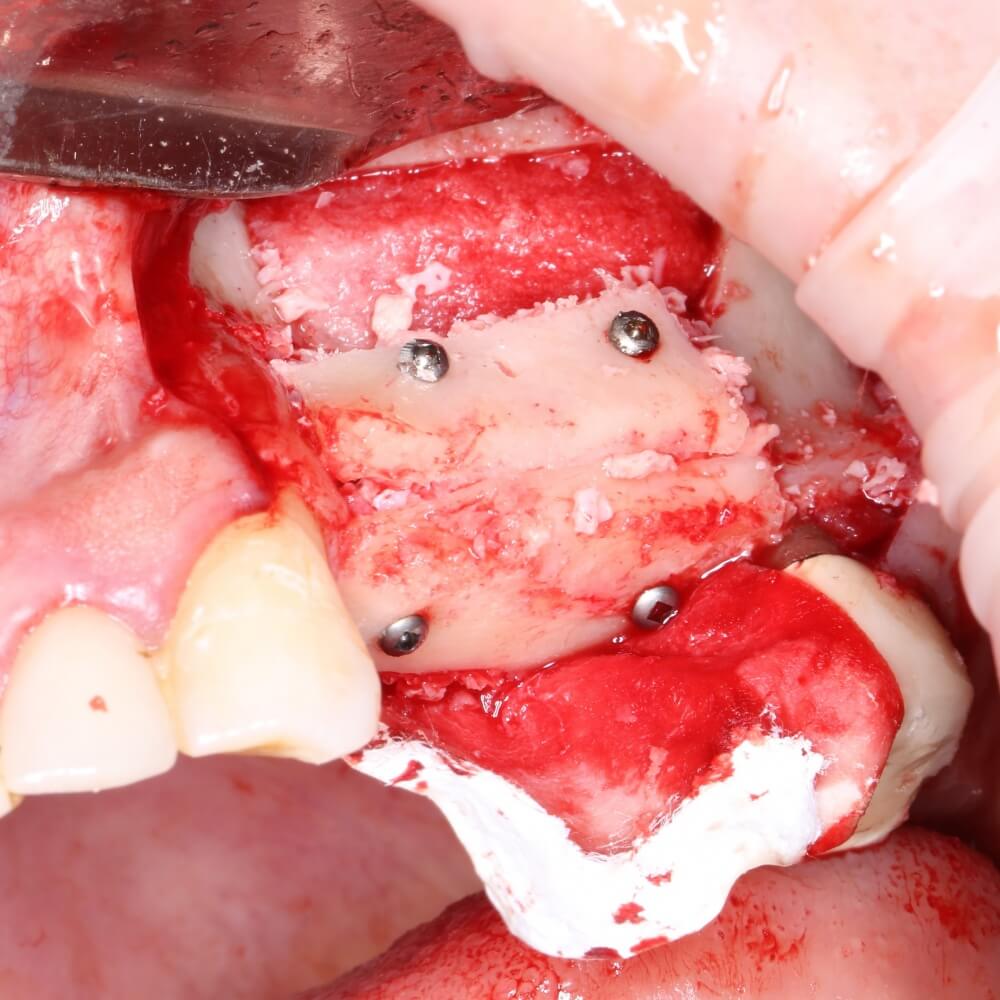

Я зафиксировал костный блок практически без адаптации на несколько винтов. Обрати внимание, что винты находятся в зоне, где не планируется установка имплантатов. Фиксация должна быть надежной, поскольку мне еще предстояла подготовка лунок для имплантатов. Трех винтов для этого вполне достаточно.

Напомню, что для этой работы я выбрал субкрестальные имплантаты Ankylos C/X. Они прекрасно сочетаются с любым методом остеопластики.

Глянем на то, что получилось:

Осталось адаптировать костный блок (убрать острые края), проверить его фиксацию и, при необходимости, добавить винты. Десятисекундное дело.

Изоляция области аутографта и имплантатов барьерной мембраной.

Конкретно в этом клиническом случае между костным аутотрансплантатом, ложем и имплантатами есть пустое пространство. Если его не изолировать от мягких тканей, они прорастут и осложнят интеграцию аутографта. Поэтому я решил перекрыть костный блок барьерной мембраной, пусть это делает хирургическую операцию немного дороже.

— ты знаешь, что барьерная мембрана может выполнять две функции, каркасную и изолирующую. Первая функция требует обязательной фиксации и натяжения, вторая — нет. В нашем случае «каркасом» регенерата является костный блок, а барьерная мембрана нужна только для изоляции. Поэтому она не требует натяжения и фиксации пинами.

После я внимательно проверил, что костный блок и имплантаты полностью перекрыты. Теперь рану можно ушивать.